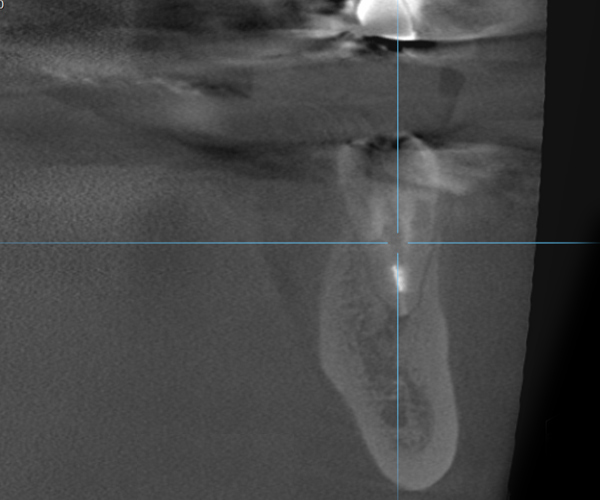

症例2歯性上顎洞炎(副鼻腔炎)

Before

歯性上顎洞炎(副鼻腔炎)

根尖病巣により洞底膜がラッパ状に開いている。

After

6ヶ月後のCT

洞底膜はきれいに再生され病巣は消失しております。